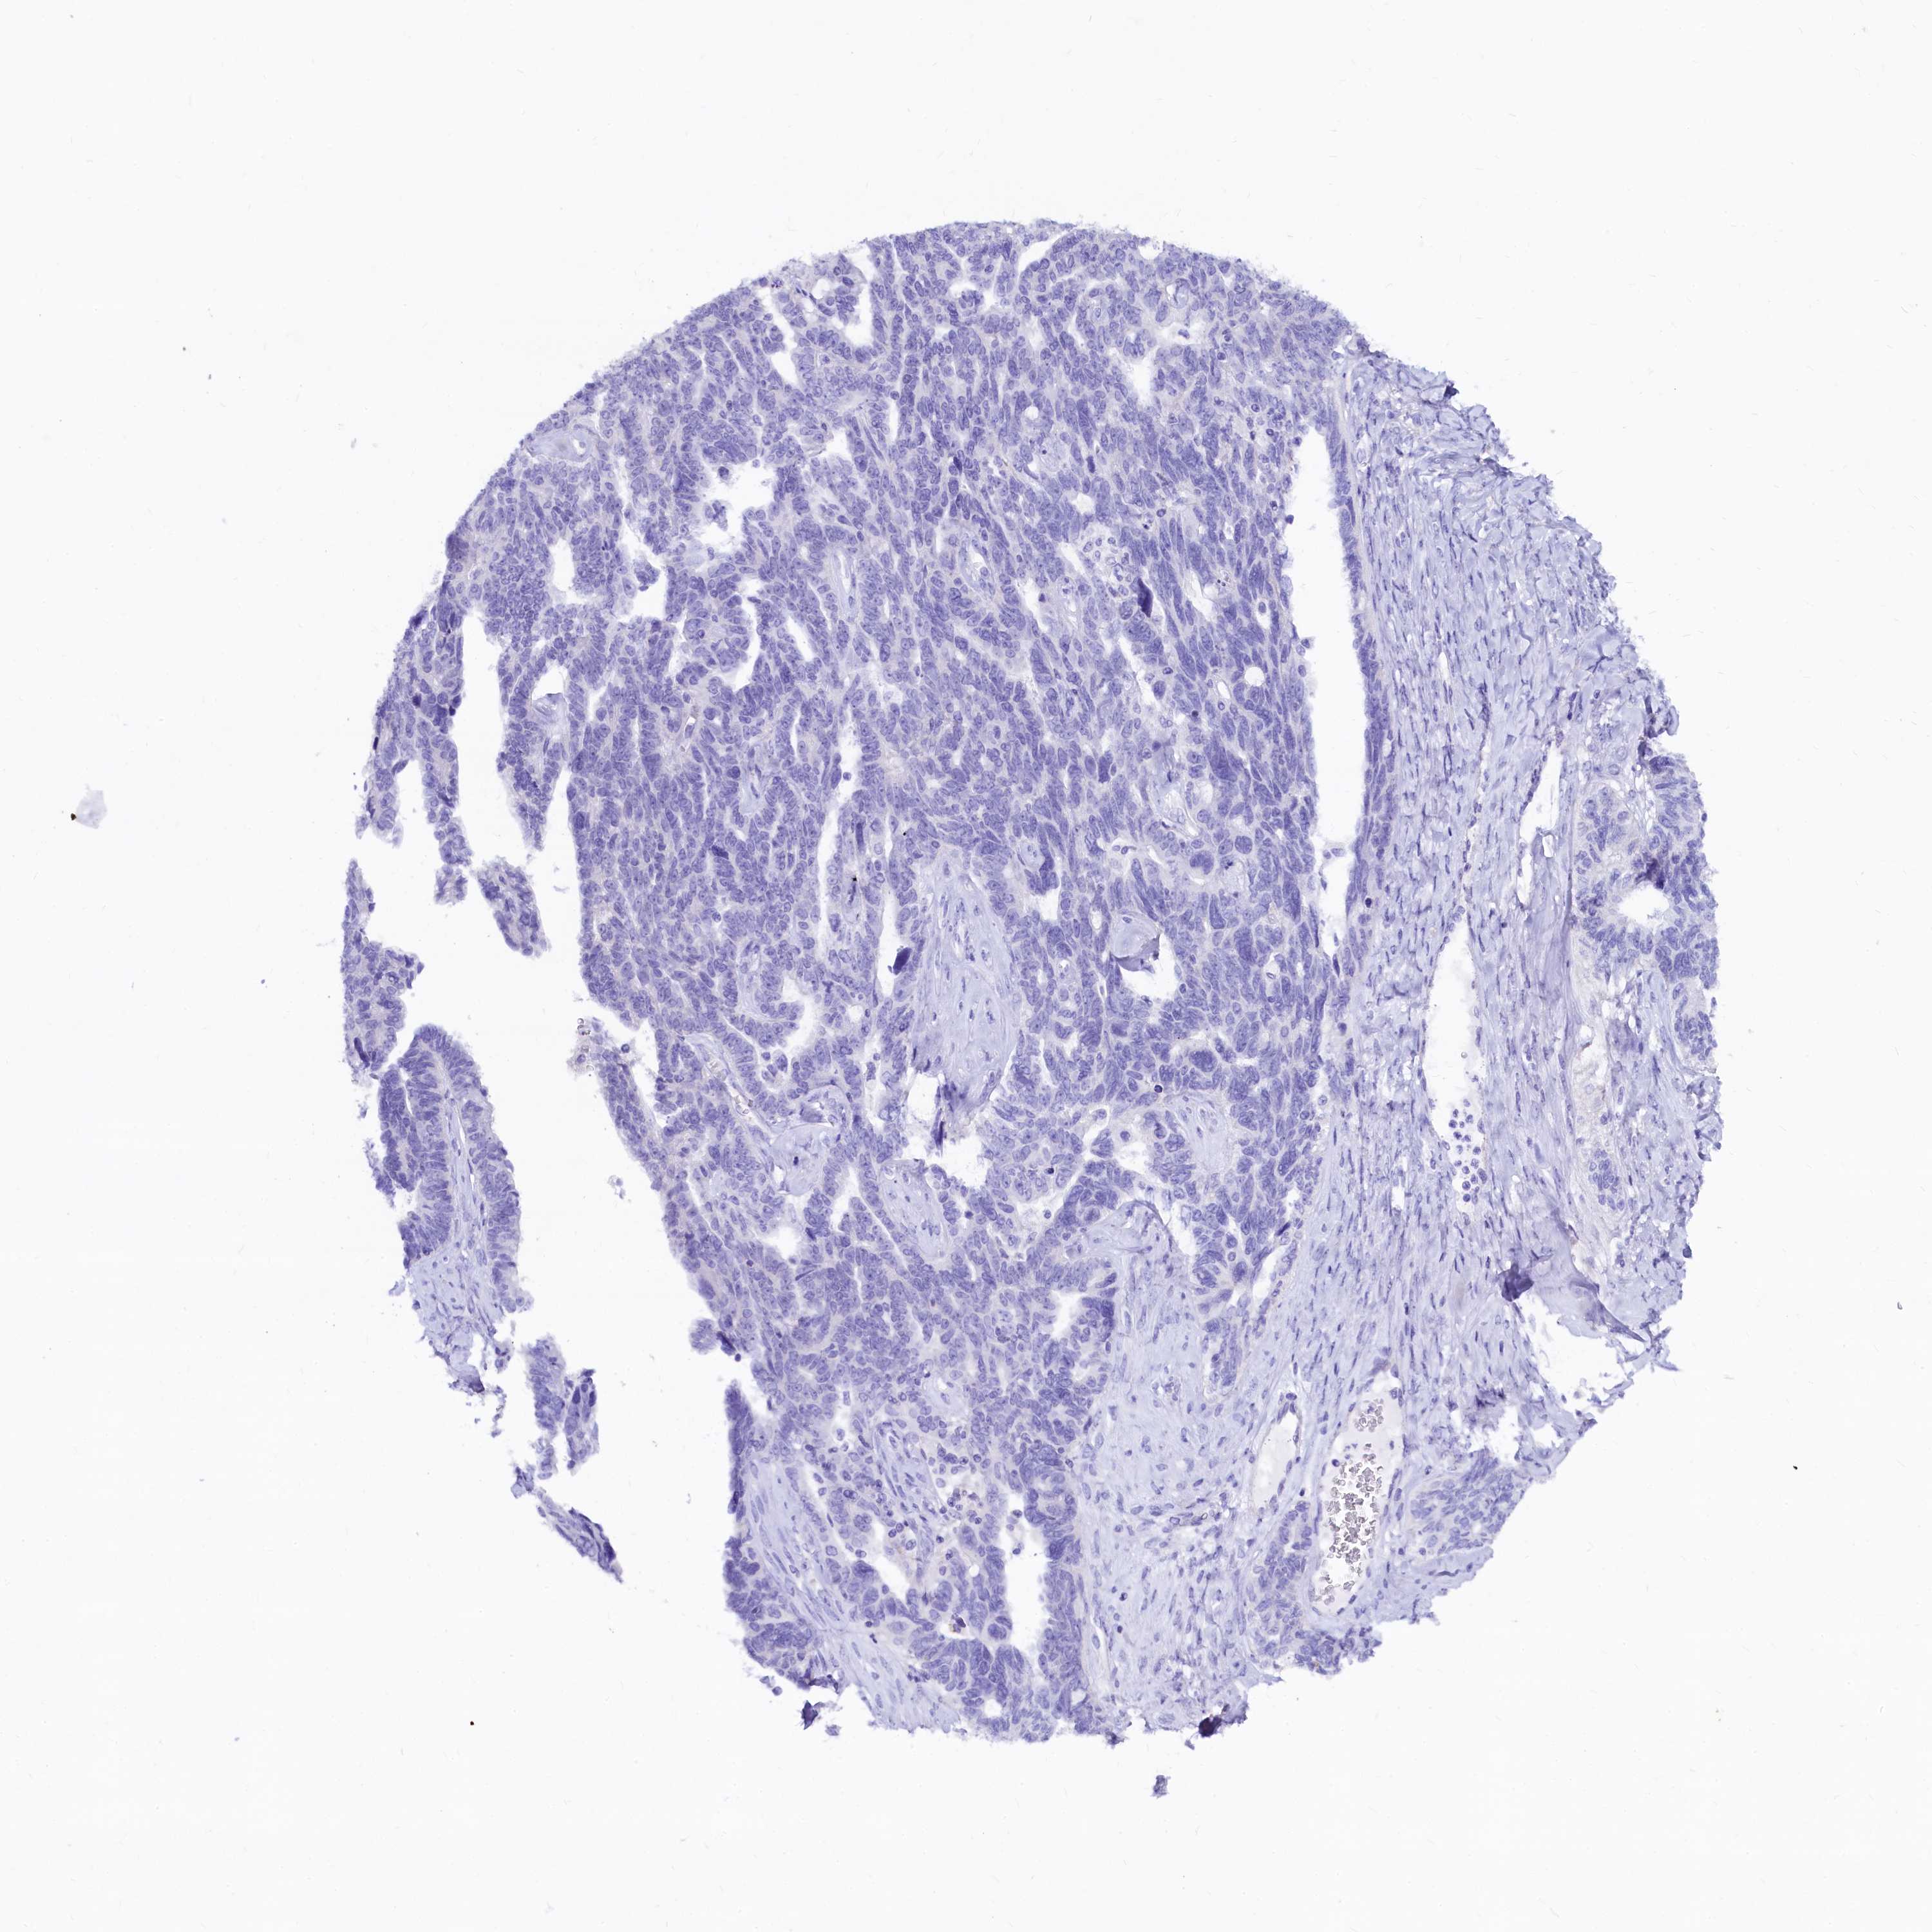

OVARIAN CANCER - Protein expressioni

A mouse-over function shows sample information and annotation data. Click on an image to view it in a full screen mode. Samples can be filtered based on level of antibody staining by selecting one or several of the following categories: high, medium, low and not detected. The assay and annotation is described here.

Note that samples used for immunohistochemistry by the Human Protein Atlas do not correspond to samples in the TCGA dataset.

Antibody stainingi

Antibody staining in the annotated cell types in the current human tissue is reported as not detected, low, medium, or high, based on conventional immunohistochemistry profiling in selected tissues. This score is based on the combination of the staining intensity and fraction of stained cells.

Each image is clickable and will lead to virtual microscopy that enables deeper exploration of all samples and also displays staining intensity scores, fraction scores and subcellular localization as well as patient and tissue information for each sample.

Antibody HPA041301

Antibody HPA044239

Staining

High

Medium

Low

Not detected

Intensity

Strong

Moderate

Weak

Negative

Quantity

>75%

75%-25%

<25%

None

Location

Nuclear

Cytoplasmic/membranous

Cytoplasmic/membranous,nuclear

Cystadenocarcinoma, serous, NOS

Carcinoma, endometroid

Cystadenocarcinoma, mucinous, NOS

Carcinoma, NOS